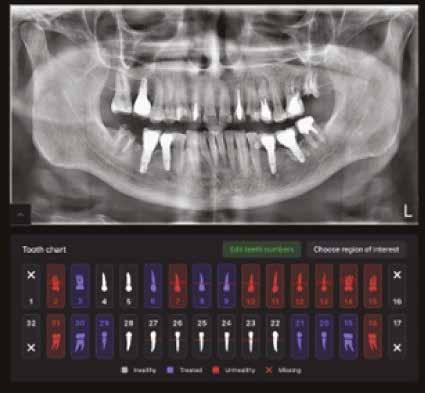

MI Diagnosztika

Új dimenzió a CBCT, a fogászati röntgenek és a kefalometriai felvételek diagnosztikájában a MESTERSÉGES

INTELLIGENCIA erejével csak a VIP DENTALBAN!

Dentális státusz elemzése mesterséges intelligencia által CBCT felvételen.

Panorámaröntgen elemzése mesterséges intelligencia által.

Kefalometriai elemzés és pontbejelölés mesterséges intelligencia által.

Legyen az Ön rendelője a fogászati ellátás innovatív központja, és velünk együtt biztosítsa a legmagasabb szintű diagnosztikai szolgáltatást az MI által támogatott elemzésünkkel.